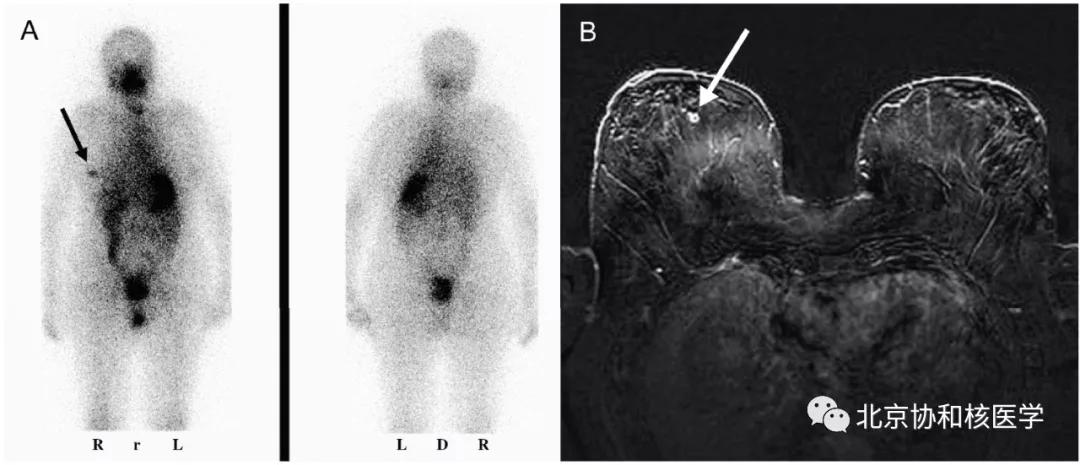

乳腺良性纤维瘤碘摄取: